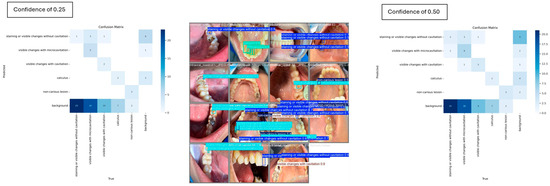

For the carious and non-carious lesion classes, YOLOv8 demonstrated strong performance in detecting visible changes associated with cavitation, consistently achieving 100% precision. However, at a confidence threshold of 0.5, the model completely failed to detect instances of the calculus class, yielding 0% mAP, precision and recall. When the threshold was reduced to 0.25, detection performance improved modestly, with the calculus class achieving an mAP of 16.7%. The pairwise confusion matrix distribution across the two thresholds is illustrated in Figure 6, highlighting the impact of threshold adjustment on class-specific detection outcomes.

Figure 6. Individual misclassification distribution across the two confidence thresholds.